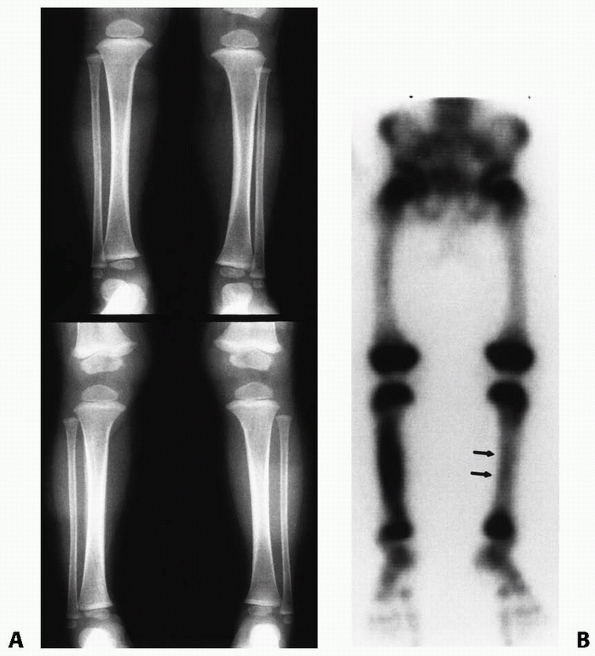

Support for this theory includes quantitative bone scans performed

months after proximal tibial metaphyseal fractures that have shown

increased tracer uptake in the medial aspect of the physis compared

with the lateral aspect.154 Ogden109

identified an increase in the collateral geniculate vascularity to the

medial proximal tibia in a cadaver angiography study of a 5-year-old

child with a previous fracture. This further supports the theory that

medial overgrowth occurs secondary to an increase in the blood flow

supplying the medial aspect of the proximal tibia following injury.101

valga is one of slow progression of the deformity, followed by gradual

restoration of normal alignment over time. Zionts and Mac-Ewen155 followed 7 children with progressive valgus deformities of the tibia for an average of 39 months after metaphyseal fractures (Fig. 25-5).

Most of the deformity developed during the first year after injury. The

tibia continued to angulate at a slower rate for up to 17 months after

injury. Six of their 7 patients

had spontaneous clinical corrections. At follow-up, all children had less than a 10-degree deformity.

FIGURE 25-8 Developmental valgus after a proximal tibial metaphyseal fracture and subsequent corrective osteotomy. A.

Radiograph taken 6 months after a fracture of the proximal tibia. The injury was nondisplaced. The scar from the initial proximal metaphyseal fracture is still seen (arrow). This child developed a moderate valgus deformity of the tibia within 6 months of fracture. B. A proximal tibial corrective osteotomy was performed. C. Two months postoperatively, the osteotomy was healed and the deformity corrected. D. Five months later, there was a recurrent valgus deformity of 13 degrees. (Courtesy of John J.J. Gugenheim, MD.) |